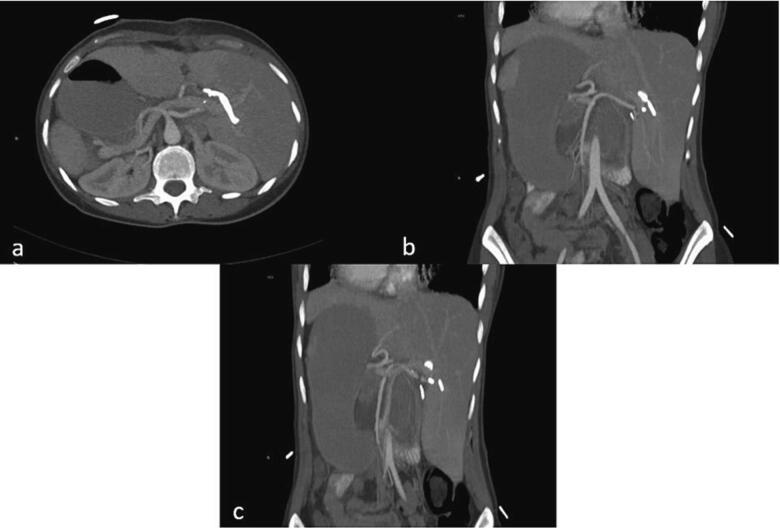

- A contrast-enhanced CT scan confirmed the appropriate positioning of the PTC catheters and identified abnormal arterial anatomy, including a replaced right hepatic artery (RHA) originating from the superior mesenteric artery (SMA) (Fig. 3a), a replaced left hepatic artery (LHA) originating from the gastroduodenal artery (Fig. 3b), and an accessory left hepatic artery originating from the left gastric artery (Fig. 3c).